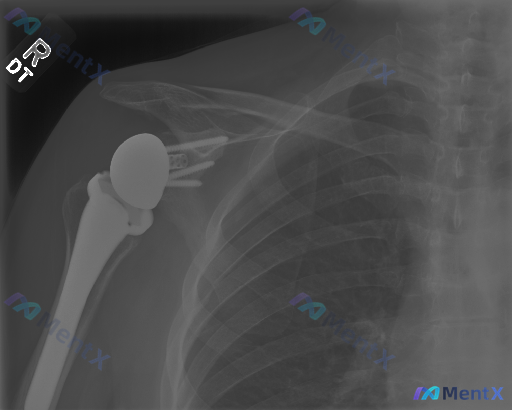

这张右肩关节置换术后X光片,能看到明确的病理性异常吗?

影像核心所见(仅基于这份单时点X光):

- 可见右肩关节假体(肱骨侧柄+球头、关节盂侧底座+螺钉),位置在位

- 假体-骨界面贴合紧密,未见明显透亮线(松动征象)

- 关节对位正常,无半脱位/移位

- 周围骨质密度均匀,未见明显破坏或骨溶解

- 软组织轮廓清晰,无明显肿胀或钙化